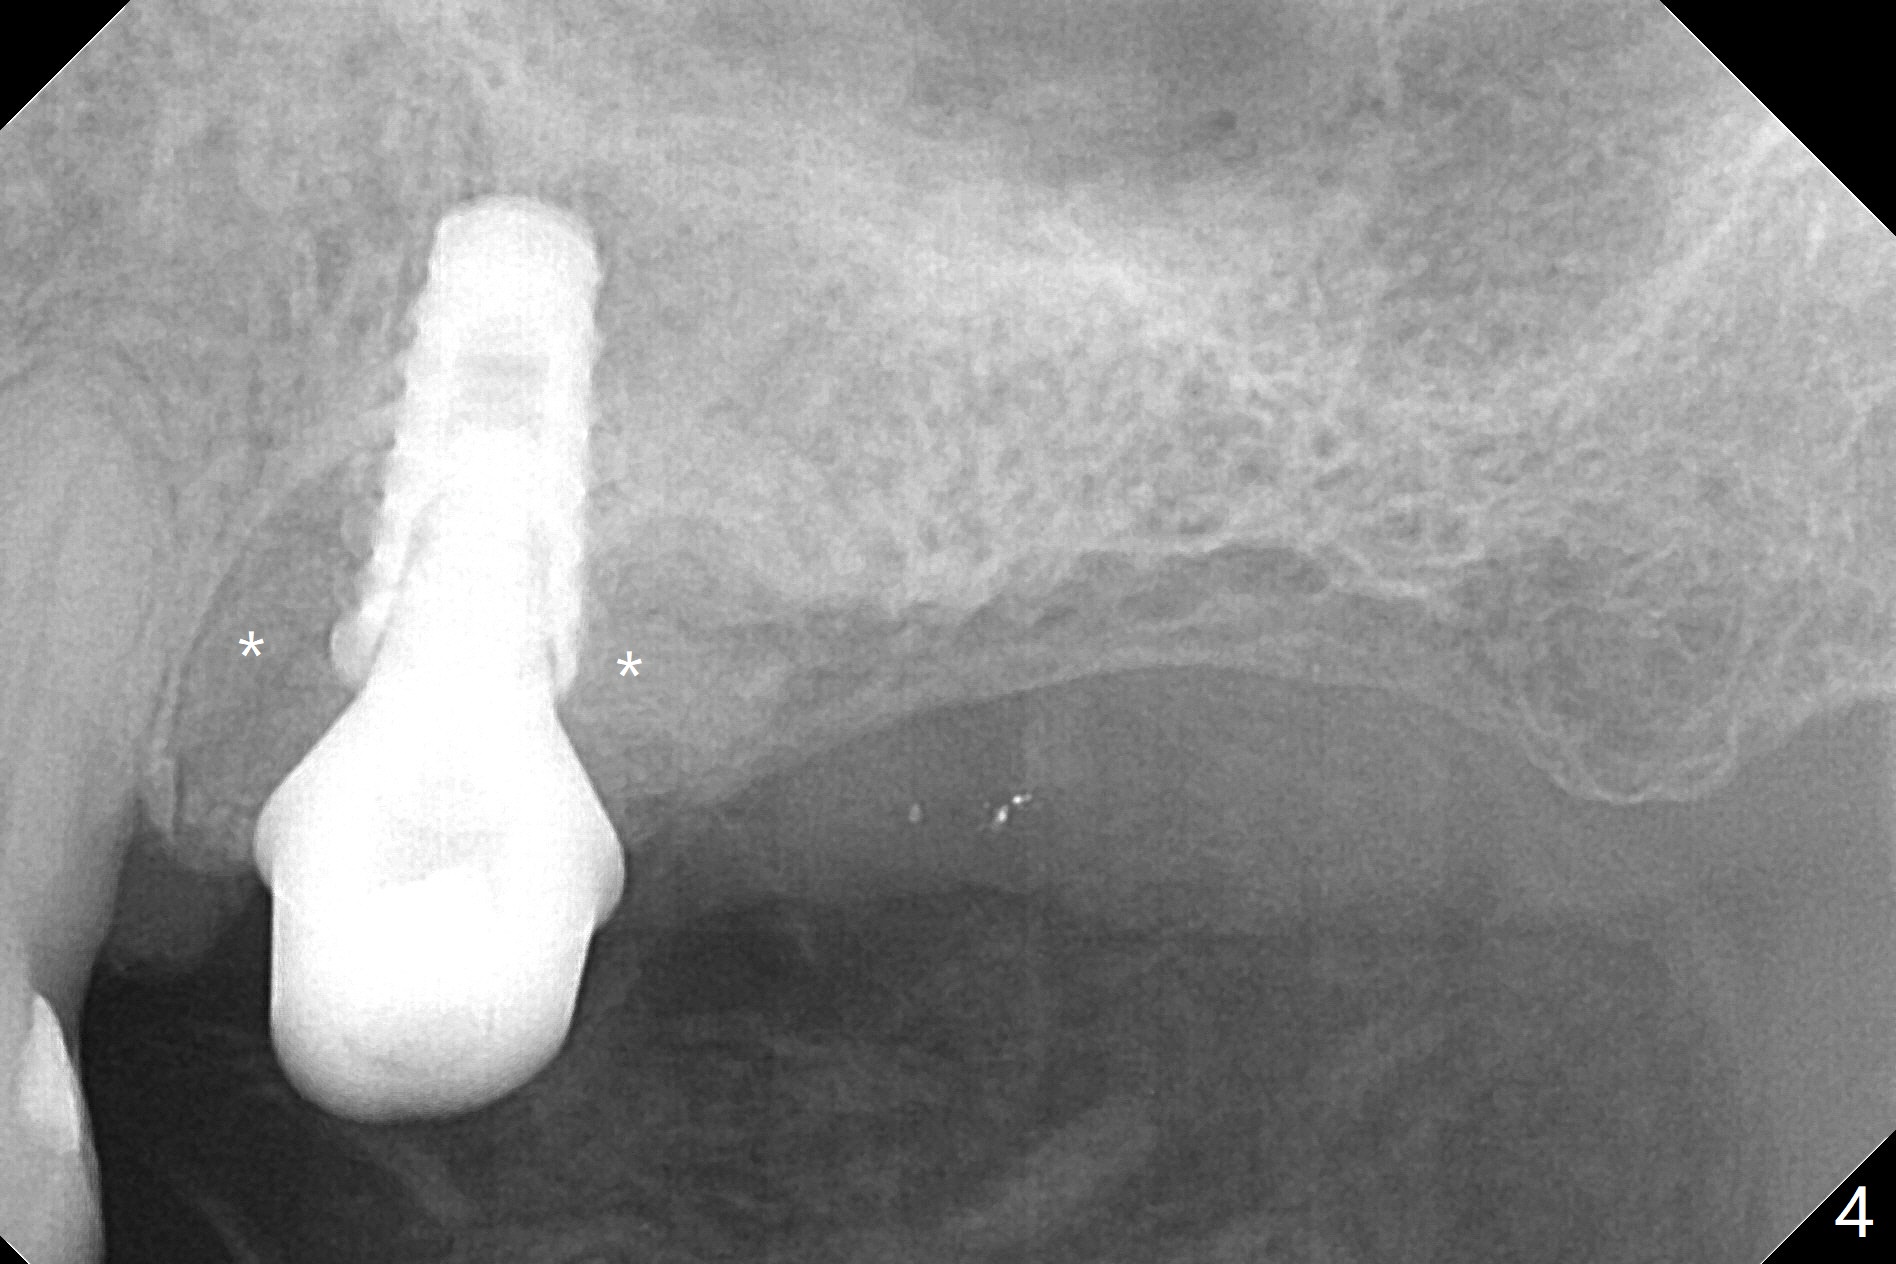

After extraction of the tooth #14 (Fig.1) and removal of granulation tissue associated with a distal fistula, a 1.6 mm drill is used to initiate osteotomy in the septum for 9 mm, followed by insertion of a 7 mm long parallel pin (Fig.2). The length of the subsequential osteotomy is 11 mm until 4.8 mm in diameter (overprep as will be shown below). The bone is hard so that sinus lift fails with 4.8 mm Magic Expander. Since a 5x9 mm dummy implant is placed with stability, a definitive implant with the same dimension is chosen with >50 Ncm (Fig.3,4). Prior to and after abutment placement, Vera graft is placed (*). The provisional perforates with loose abutment 3.5 months postop. A 6x4 mm healing abutment is placed. Osteointegration occurs 4 months postop (Fig.5,6).